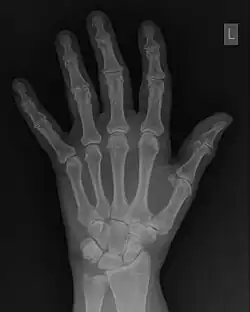

The conventional way of interpreting radiographic images in medicine is to regard them as representations of human anatomy. In the mathematical analysis of these images, however, we can interpret them as fluctuations of signal amplitude in space, as demonstrated in Figure 1.23.

FFTs can also be calculated in two-dimensions to give results such as those in Figure 1.27. Since Fourier analysis generates results in terms of both positive and negative spatial frequencies, these can be plotted in the form of a 2D image so that the maximum frequency lies at the origin and those for the horizontal and vertical directions are shown increasing towards that origin. The modulation at different spatial frequencies is represented using a grey-scale. Low frequency bands can be seen along the horizontal axis in the figure, for example, representing the horizontal periodicity of image data from the fingers, while finer bands along the y-dimension are indicative of a periodicity of image data from the various metacarpophalangeal joints. Higher frequency features can also be seen running diagonally in this 2D-FFT, representative of the trabecular structure of the bones, for example.

The essence of this approach is that it can be used to produce a range of image processing effects by enhancing and/or suppressing features in the 2D-FFT and then converting the result back into the spatial domain using the IFT, as illustrated in Figure 1.28. Such image manipulations are considered in more detail in a later chapter. Note that the form of image processing demonstrated in the figure is for purely illustrative purposes and bears no direct medical significance.